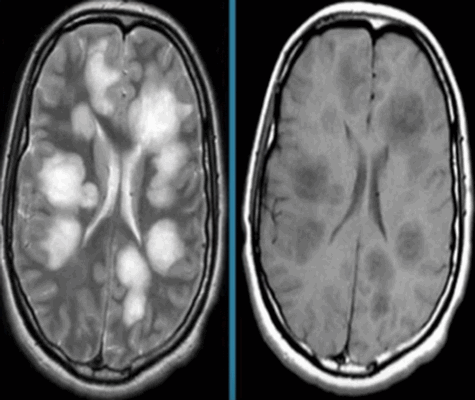

МР-снимок церебральных структур в режиме Т2 (аксиальная проекция)

Анализ результатов МРТ головного мозга заключается в расшифровке снимков, выполненных в трех плоскостях (аксиальной, сагиттальной и коронарной) с шагом среза от 1 мм. Сканирование области интереса проводят в разных режимах. Основными являются Т1 и Т2 ВИ. Отличие режимов друг от друга состоит в отображении структур, содержащих жидкость. Ткань с большим количеством воды в режиме Т1 имеет на фото темную окраску, в Т2 - светлую. По-разному выглядит серое вещество головного мозга. В последовательности Т2 субстанция визуализируется в светлом оттенке.

МР-снимок головного мозга в режиме Т1 (аксиальная проекция)